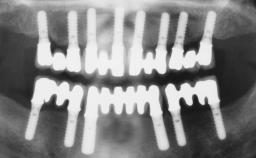

Conventional Loading of Eight Implants in the Maxilla and Final Restoration with a Full-Arch Gold-Ceramic FDP

# of Implants 8

Type of Implants One-Piece

Bone Augmentation Horizontal|Staged|Vertical

Augmentation Materials Autogenous block(s)